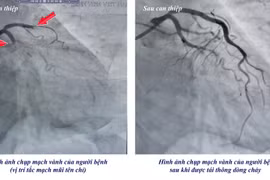

Ê-kíp khẩn trương can thiệp mạch vành bằng hệ thống máy Philips hiện đại hàng đầu thế giới, mạch máu được tái thông hiệu quả, chức năng tim được bảo tồn.